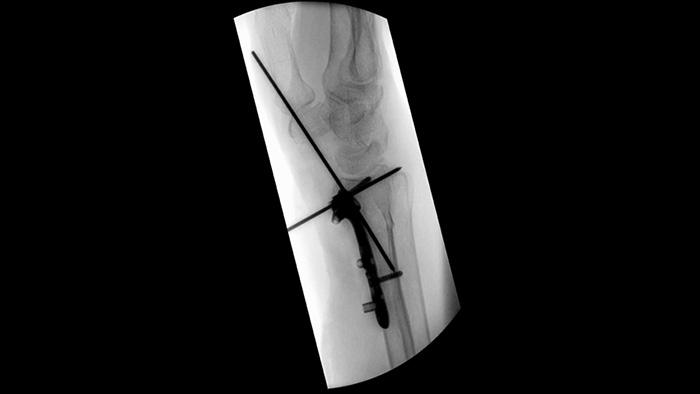

MetalSmart

Mejora automática de la imagen

MetalSmart excluye automáticamente los artefactos metálicos causados por los implantes metálicos para proporcionar una mayor calidad de imagen y un control eficiente de la dosis para los procedimientos ortopédicos y para los pacientes con implantes metálicos, en comparación con los sistemas sin exclusión de metales. BodySmart favorece la obtención de imágenes correctas a la primera y la eficiencia de la dosis ya que adapta, de forma automática, el campo de medición a la zona de interés.